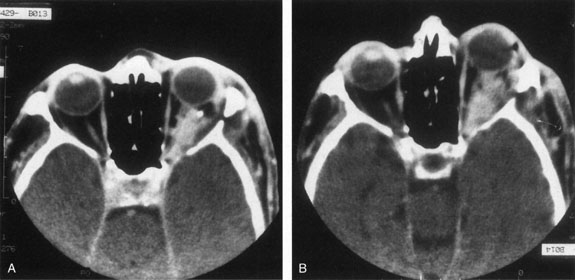

There are no pathognomonic ultrasonography, CT, or MRI findings. A-scan ultrasonography shows well-delineated regular structures with low internal reflectivity and minimal attenuation owing to the congested pools of blood in the dilated veins. Doppler demonstrates flow within the lesion.58 Computed tomography may show abnormally dilated, irregular veins with uniform contrast enhancement or, when there has been hemorrhage, multilobular lesions.58 As the VFM may not be visualized when collapsed, direct coronal scans should be obtained in the prone position or during the Valsalva maneuver to distend the lesions (Fig. 14). Spiral CT with a single breath-holding technique may be useful in confirming an increase in size of the lesion during the Valsalva maneuver.104 The majority of venous malformations typically occupy the superomedial orbit in the area of the superior ophthalmic vein, followed by the inferolateral quadrant.95,104 In their study of 158 patients with NFM and VFM, Wright and colleagues found 45% with phleboliths.95 Enlargement of the affected orbit also may be seen.95 Obtaining MRI scans before and during a Valsalva maneuver may show distensibility, and uniform enhancement occurs.58 Venography is seldom used now because of the availability of other imaging modalities. Carotid angiography may demonstrate the VFM and can detect venous enlargement consequent to arteriovenous shunting.

Fig. 14. Orbital venous flow malformation. Axial computed tomography scan showing an ill-defined, dense, inhomogeneous orbital lesion with the patient in a supine position (A). Note the phlebolith, which indicates venous stagnation. As the venous flow malformation distends with the patient in the prone position, the lesion enlarges (B). (Courtesy of Dr. John V. Linberg, University of West Virginia, Morgantown, WV)